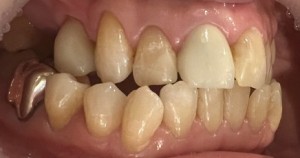

お口の中を拝見したところ、右上5・6が無く、右上4も下の歯とは噛んでいない状態でした。このことから、右側の噛み合わせが不安定なため、痛みが生じていることがわかりました。

治療を始める前に患者様の歯型を取り、模型を使用しながら左右での『噛む力のバランスが崩れてしまっている』ことを伝えました。

今回、様々な治療選択の中から、右上4番は被せもので、その奥は義歯(バネが目立たない)で修復することになりました。